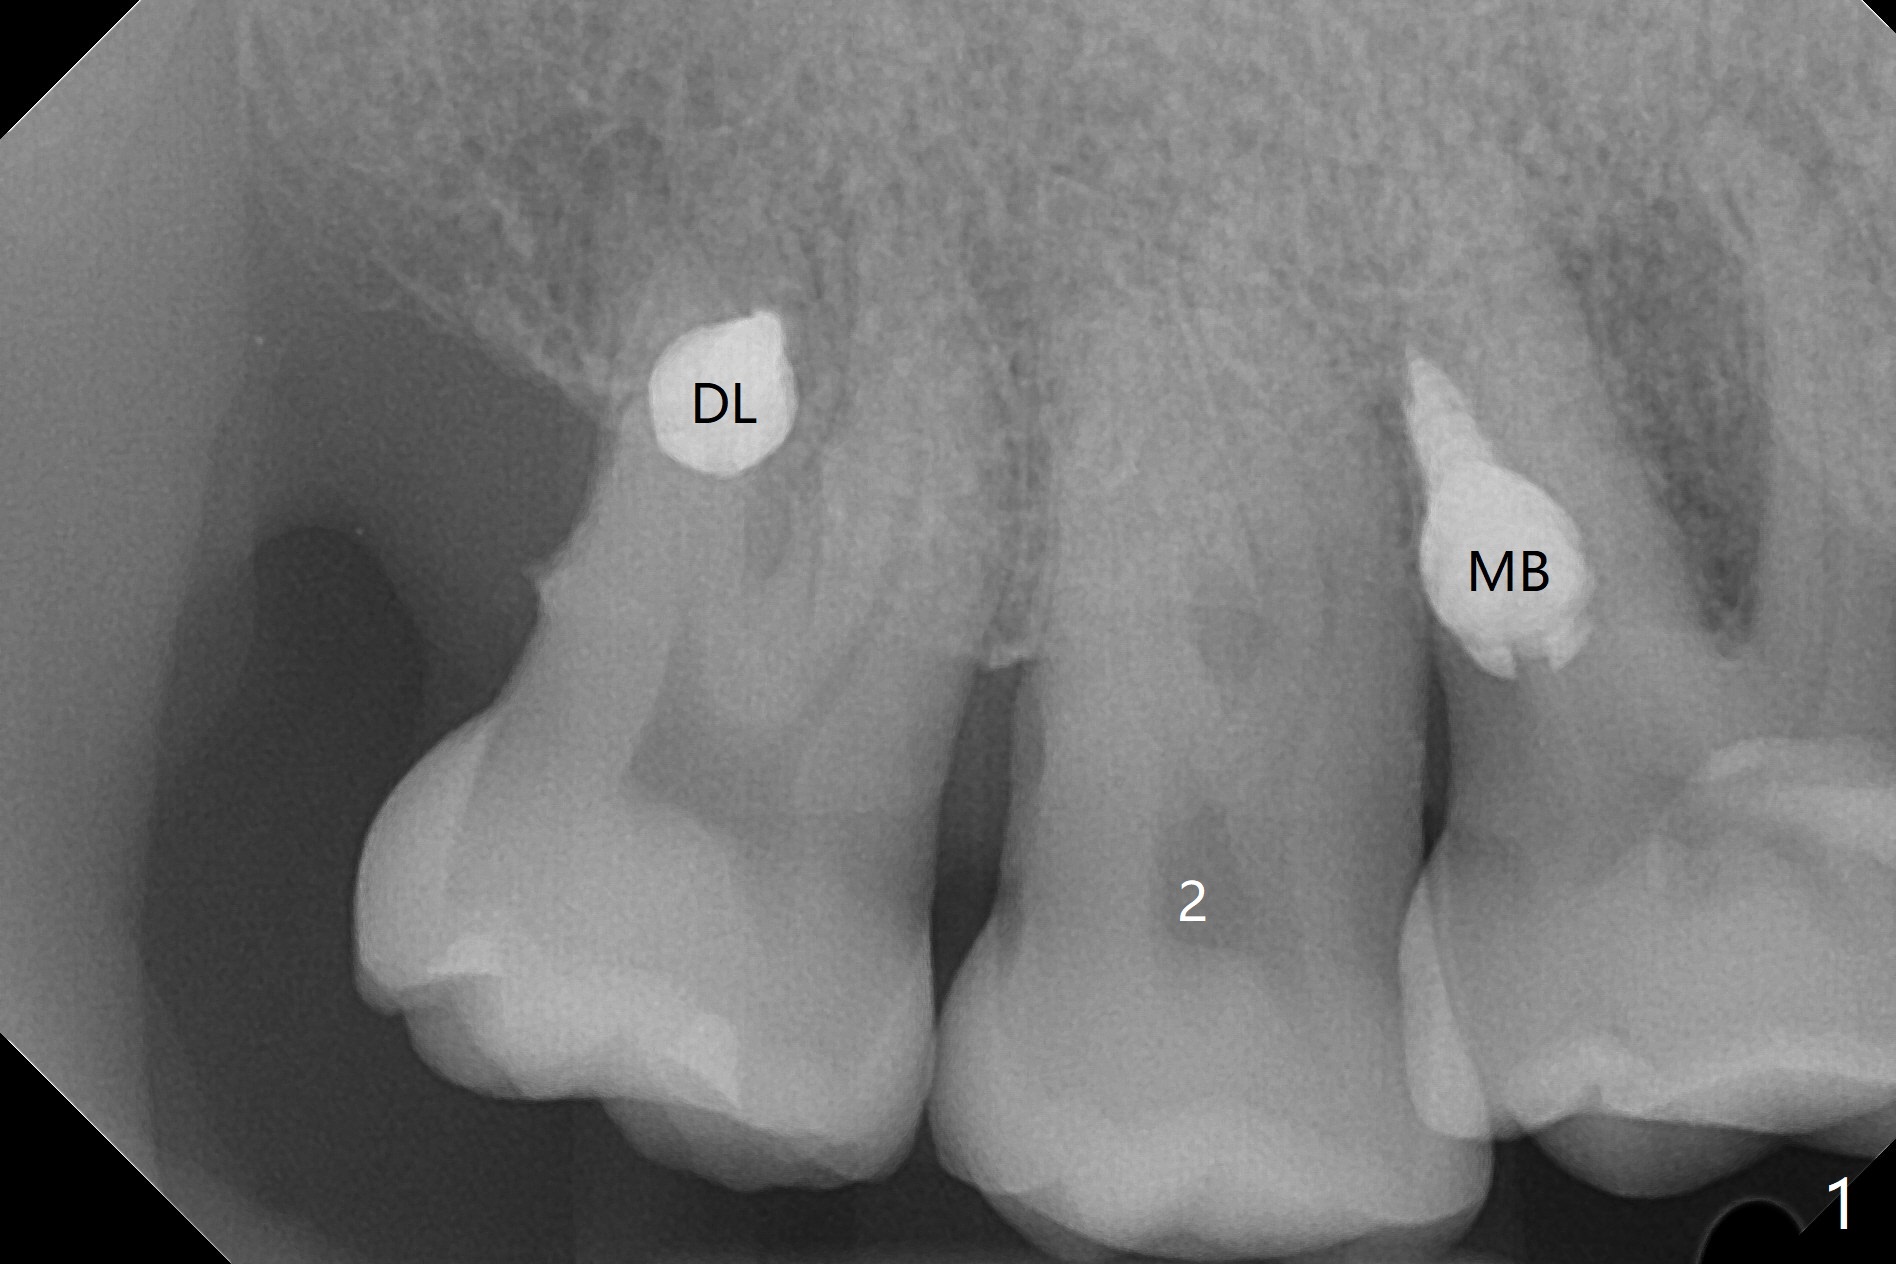

When 6 and 8 mm Tomas pins are initially placed mesiobuccal (MB) and distolingual (DL) to the supraerupted tooth #2, PA is taken (Fig.1), which shows that the DL one seems too distal. The mini implant is removed and placed more mesial (Fig.2, 7 (^: original entry)). When the patient experiences a little pain as the DL implant is being placed deeper with minimal local anesthetic, CT is taken. In fact the latter is between the apices of the teeth #1 and 2 (Fig.3 (L: lingual view of 3D image)). The implant is later placed deeper with minor angular change as well as more anesthetic. There is an advantage to place the miniimplants apically; there is more space. But the MB implant is a little bit mesial (Fig.4). After withdrawal, the trajectory of the implant is changed somewhat as indicated by a red arrow in Fig.5). Note the apical placement of the minimplants (close to mucogingival junction, Fig.6,7).